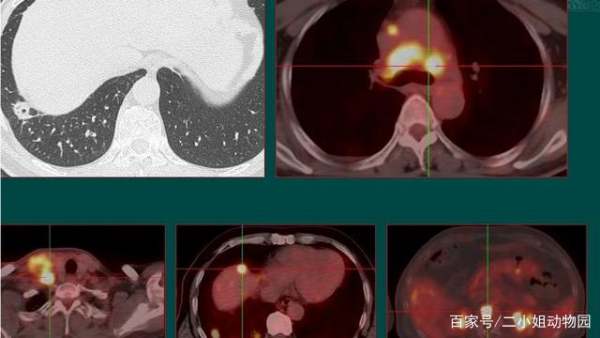

这是山东肿瘤医院黄教授分享的一个病例,老烟民,不足5毫米的磨玻璃小结节,结果仅仅过了一年,结节增大数倍,并且发生广泛转移:

这是他的PET-CT图像,黄色的高浓聚区都是转移的淋巴结还有肾上腺转移,已经没有手术机会了。所以我们对于首次发现的肺结节,尤其是老烟民,第1次复查间隔要短一点。